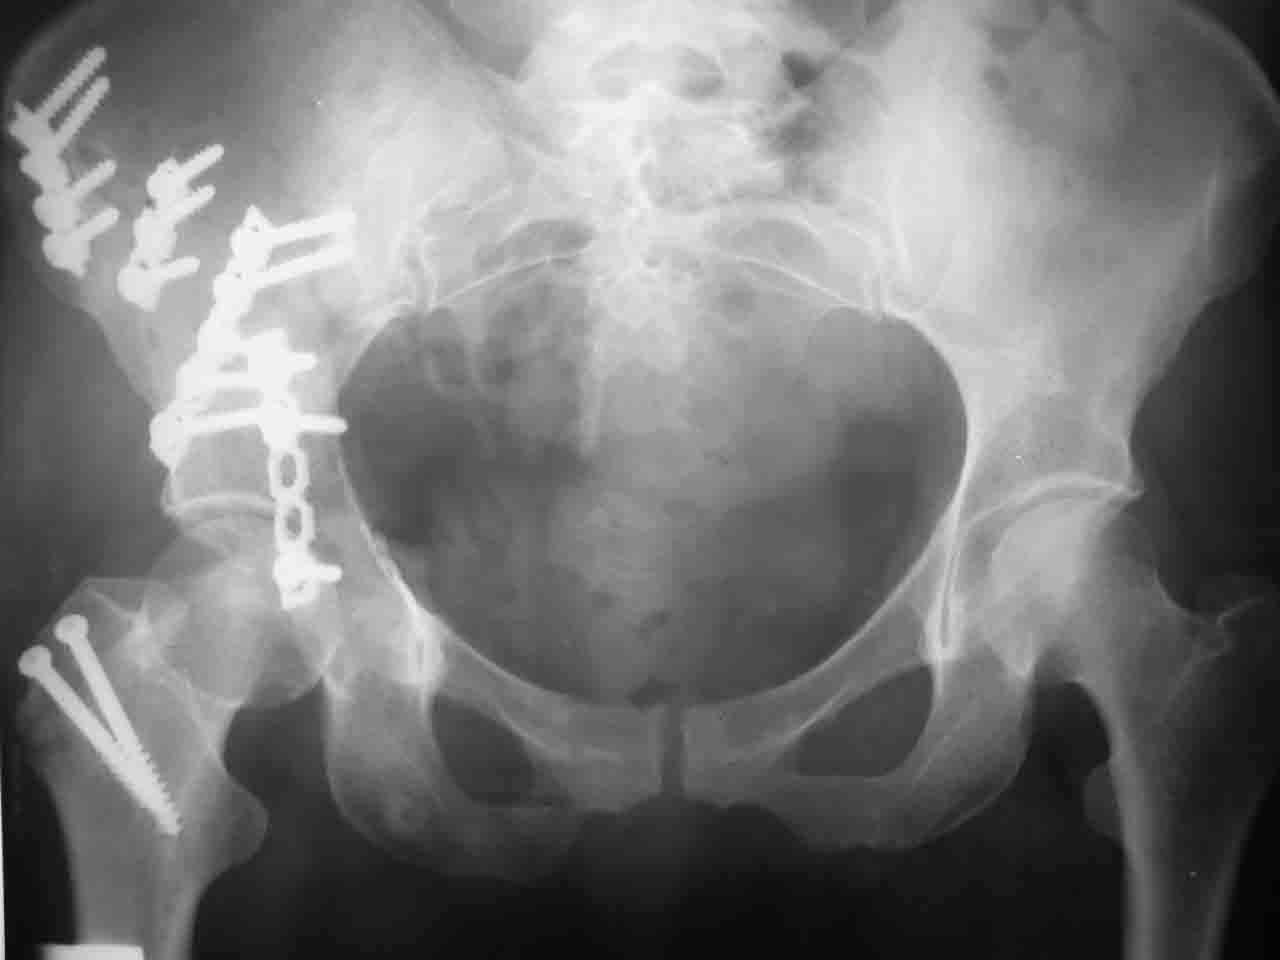

А какой отдел вертлужной впадины более важен передний или задний? Чем был обусловлен выбор доступа к суставу? Проще говоря, почему вы пошли передним доступом на двухколонный перелом? Мне понятны ваши сомнения, когда не удется сделать все что хотелось бы. В данном случае доступ должен быть чрезвертельным боковым (как и советовал Рунков) или двумя доступами.

Сложностью, ассоциативностью характера перелома, я бы с радостью воспользовался мининвазивной перкутанной фиксацией винтами, но боюсь, что результат был бы ещё хуже, техникой непрямой репозиции перелома не владею, поэтому пытаясь получить анатомичную впадину приходится широко открывать, по крайней мере пока, а дальше буду пытаться уменьшать пространство...

> передним доступом на двухколонный перелом?

Илеофеморальный доступ не совсем передний и сравнительно с илеоингвинальным, и Кохера-Лангенбека открывает весь наружный таз кроме самых передних отделов лонных костей, фиксацию которых я не ставил в задачу. Обширность диссекции, большая длительность операции и более высокий риск гетерооссификации - отрицательные моменты в обмен на возможность легче ориентироваться.

Вопрос доступа к вертлужной впадине при остеосинтезе задача не простая. Конечно, у Летурнеля и Тайла всё давно описано, нам остается только брать на вооружение. Но сами понимаете, что не бывает двух одинаковых ситуаций, поэтому в каждом случае вопрос решается сугубо индивидуально. Наша главная цель - восстановить анатомию с нанесением минимальной дополнительной травмы тазобедреннному суставу, думаю с этим никто не поспорит. Расширенный илиофеморальный доступ уж слишком травматичен (как сказал один коллега "таз лежит отдельно, больной отдельно").Стоит ли делать из пациента анатомический препарат для того чтобы легче ориентироваться. Да и нужно ли собирать всю "мозаику"? Мы применяли при таких операциях своеобразную операционную хитрость - сначала устраняли грубое смещение крыла под гребнем с фиксацией так называемой "плавающей" пластиной (временно фиксированной на двух винтах)- доступ или продлевали боковой, или делали небольшой дополнительный разрез над гребнем. Это позволяло устранить грубое смещение и захождение отломков тела повздошной кости, что значительно облегчало репозицию и остеосинтез впадины над сводом. Основное внимание конечно же уделяли нагружаемому задне-верхнему отделу. Сообщите ваш адрес, пришлю схемы и рентгенограммы.